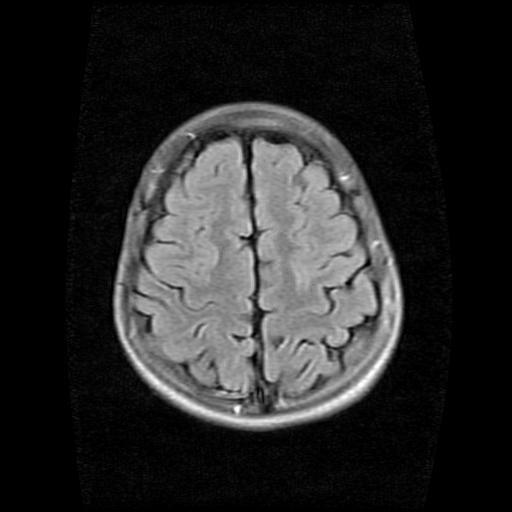

9岁女孩,三岁时诊断为癫痫,一直服丙戊酸钠,现患者一般情况良好,家长复查核磁片,看能否停药..

未见异常信号灶.

未发现异常信号。